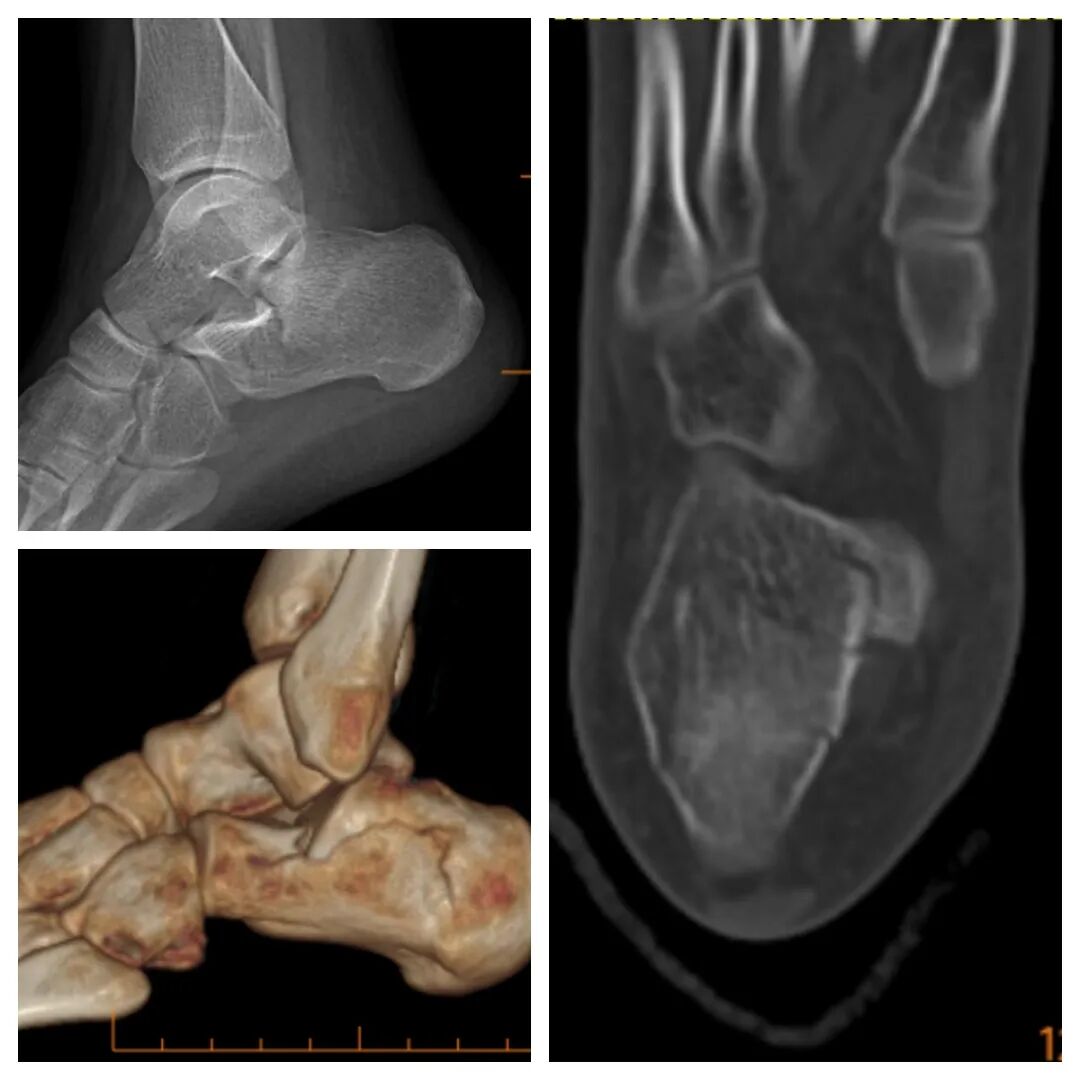

近日,一名14岁的患者因跟骨骨折,来河南大学淮河医院就诊,创伤骨科郭建阔主任团队接诊后,没有选择传统的“大刀口”,而是为患者实施“跗骨窦入路+跟骨钉中钉”的微创方案。

主切口仅3厘米;

系开封地区首次应用跟骨钉中钉内固定器械;

成功复位的同时,充分保护了软组织血运。

“跟骨钉中钉”是一种用于治疗特定类型跟骨骨折的微创髓内内固定技术。它通过一个由主钉和多枚辅助锁定螺钉组成的系统,实现对骨折部位的稳定固定。

该系统通常由1根主钉和4枚辅助钉(辅钉)组成。其核心理念是通过微创方式,在跟骨内部构建一个相互锁扣的稳定结构,因此形象地被称为“钉中钉”。

主钉:通常从跟骨结节向跟骰关节方向置入,用以维持跟骨的长度。

辅钉:通过主钉上的孔道置入,分别固定跟骨上方、外侧及载距突等关键部位,与主钉形成一个整体,构成三角形中心固定,提供强大的生物力学稳定性。